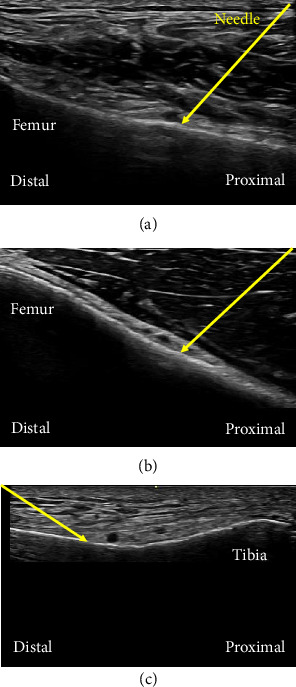

背景:全膝关节置换术(TKA)与术后剧烈疼痛相关,连续股骨三角阻滞(FTB)和腘动脉与膝关节后囊之间浸润阻滞(iPACK)已被采用。膝部神经为两种阻滞不影响的膝关节部分提供感觉,因此我们最近开始在FTB和iPACK阻滞的组合中加入膝部神经阻滞(GNBs)。在这项回顾性研究中,我们检查了gnb的加入是否对TKA患者有益。方法:我们对在我院接受TKA并接受我们的标准镇痛方案(包括连续FTB和iPACK阻滞)的患者前瞻性收集的数据进行回顾性分析。我们比较了有gnb和没有gnb的患者的手术内和术后数据,包括阻滞表现所需的时间、视觉模拟评分(VAS)疼痛评分、镇痛需求和不良事件。采用双尾Student’st检验、Mann-Whitney U检验、卡方检验和Fisher确切检验进行统计分析。结果:74例患者,其中有gnb患者41例,无gnb患者33例。患者的人口统计数据具有可比性。术后第1天,接受GNBs治疗的患者和未接受GNBs治疗的患者休息时VAS疼痛评分无差异(中位数[IQR] 20[0-36]比25 [19-45],p = 0.205)。术后两天内与术后疼痛相关的其他测量也相似。未见与阻滞相关的严重并发症。结论:这项探索性回顾性研究的结果表明,gnb在TKA患者术后早期联合持续FTB和iPACK阻滞时的额外益处(如果有的话)有限。然而,需要更大规模、更有力、更可靠的临床试验来证实目前的结果。

Background: Total knee arthroplasty (TKA) is associated with intense postoperative pain, for which continuous femoral triangle block (FTB) and infiltration between the popliteal artery and the capsule of the posterior knee (iPACK) block have been used. Genicular nerves supply sensation to a part of the knee joint that the two blocks do not affect, so we recently started adding genicular nerve blocks (GNBs) to the combination of FTB and iPACK block. In this retrospective study, we examined to see if the addition of GNBs benefited patients undergoing TKA. Methods: We conducted a retrospective analysis of data that had been collected prospectively from patients undergoing TKA and receiving our standard analgesic regimen including continuous FTB and iPACK block in our hospital. We compared patients with and without GNBs regarding intra- and postoperative data including the time needed for block performance, visual analog scale (VAS) pain scores, analgesic requirements, and adverse events. The two-tailed Student's t test, Mann-Whitney U test, chi-square test, and Fisher's exact test were used for statistical analysis. Results: Seventy-four patients including 41 and 33 patients with and without GNBs, respectively, were evaluated. The demographics of the patients were comparable. VAS pain score at rest on postoperative day 1 was not different between patients who received GNBs and those who did not (20 [0-36] vs. 25 [19-45] in median [IQR], p = 0.205). Other measurements related to postoperative pain were also similar throughout the two postoperative days. No severe complications related to blocks were observed. Conclusion: The results of this exploratory retrospective study suggest that the additional benefits of GNBs, if any, are limited for the early postoperative period when combined with continuous FTB and iPACK block in patients undergoing TKA. However, larger, sufficiently powered, and more robust clinical trials are needed to confirm the present results.